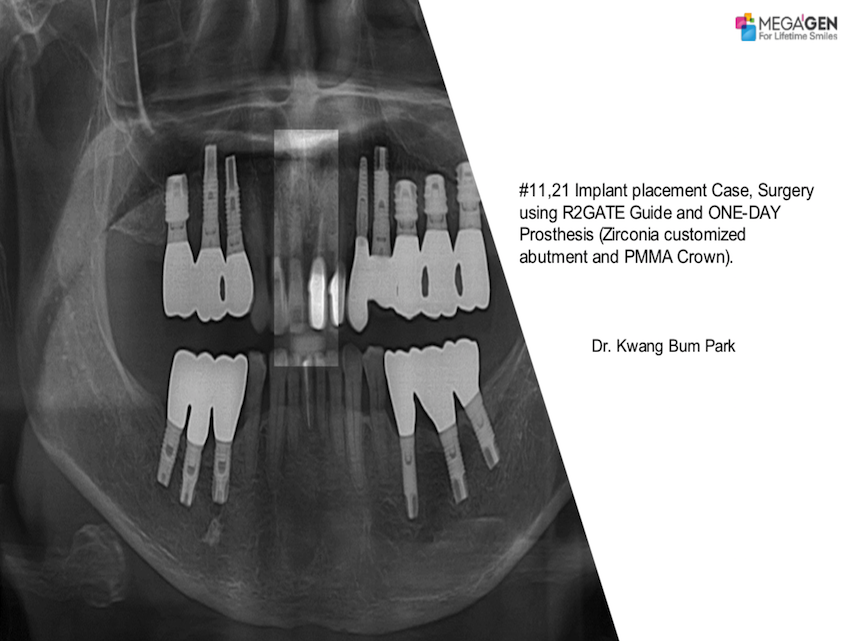

#11, 21 Implant placement Case, Surgery using R2GATE Guide and ONE-DAY Prosthesis

Dr. Kwang Bum Park,Digital ONE-DAY Implant,Maxillary Anterior,#11,#12,Immediate loading,AnyRidge,R2GATE,MEGA ISQ,R2GATE Surgical Kit(AnyRidge)

English

2019-09-26

PDF

1.23 Mb

Clinical cases

176